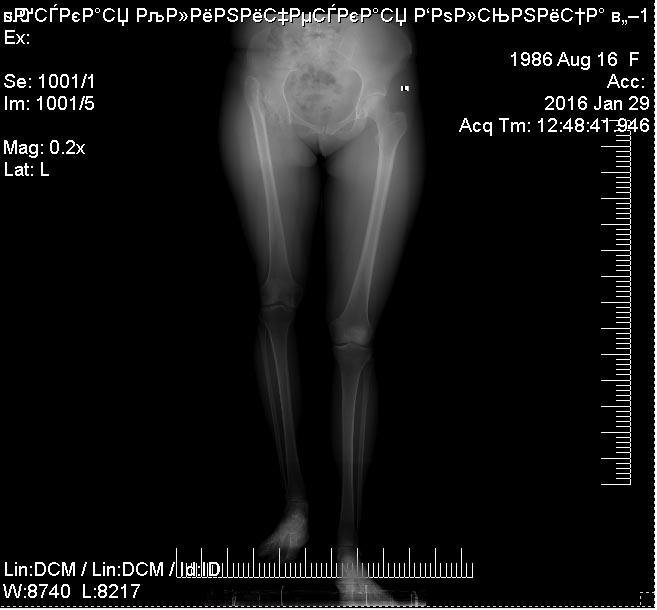

Обзорная рентгенография нижних конечностей.